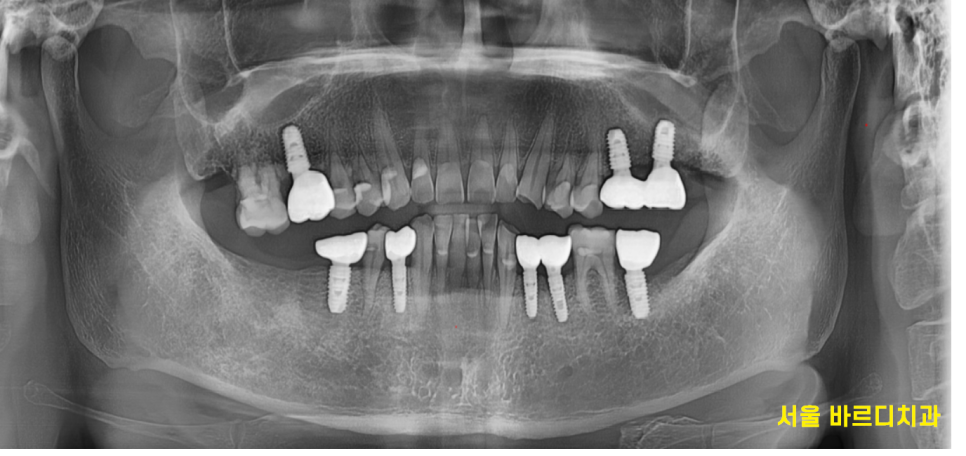

23.08.03

시간이 흘러 임플란트 기둥을 세우고

머리를 만들어 드렸습니다.

23.08.18

어금니 빠짐으로 1개 2개씩 물리던 치아가

이제 모두 물리게 해결해 드렸어요~!